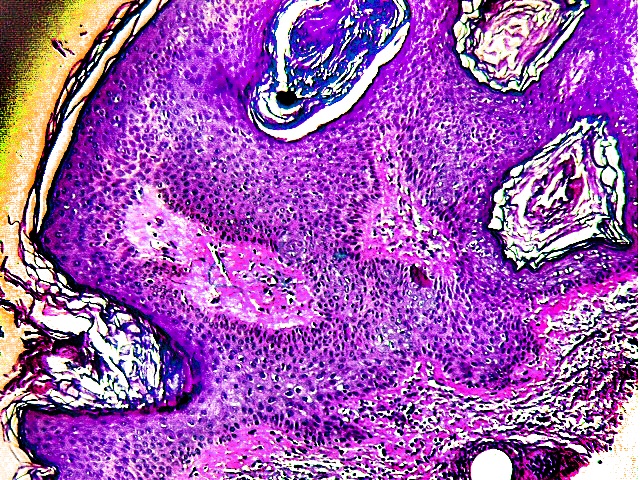

Diagnosis

Clinical findings of a person with this condition are outgrowths on the trunk and face though they could also be present on other parts of the body. One could have a few lesions but in some instances, a patient has numerous lesions. The lesions will normally differ in color. They range from black to brown though those that are thinner appear paler than others. Traumatized lesions look inflamed.

If the rate at which the outgrowths increase is very high, then it is vital that more investigation be carried out. A sample is taken for histology and other tests. According to the findings, a surgery could be the next course of action. If there is too much itching and the number of outgrowths continue to raise, it is dangerous because the growths should slowly decrease on their own or after medication. In situations where one has to take a surgery, they should completely cooperate with the doctor and not get bothered about the scars that will remain after the operation. Scars and marks will usually clear with time.